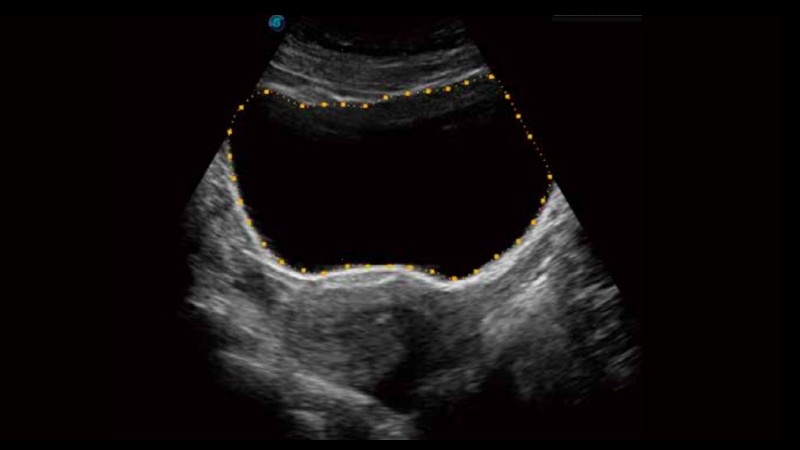

膀胱自動測量,一鍵式膀胱壁追蹤和容量測量可有效提供更精確的輪廓和結果,不受膀胱形狀和大小的影響。